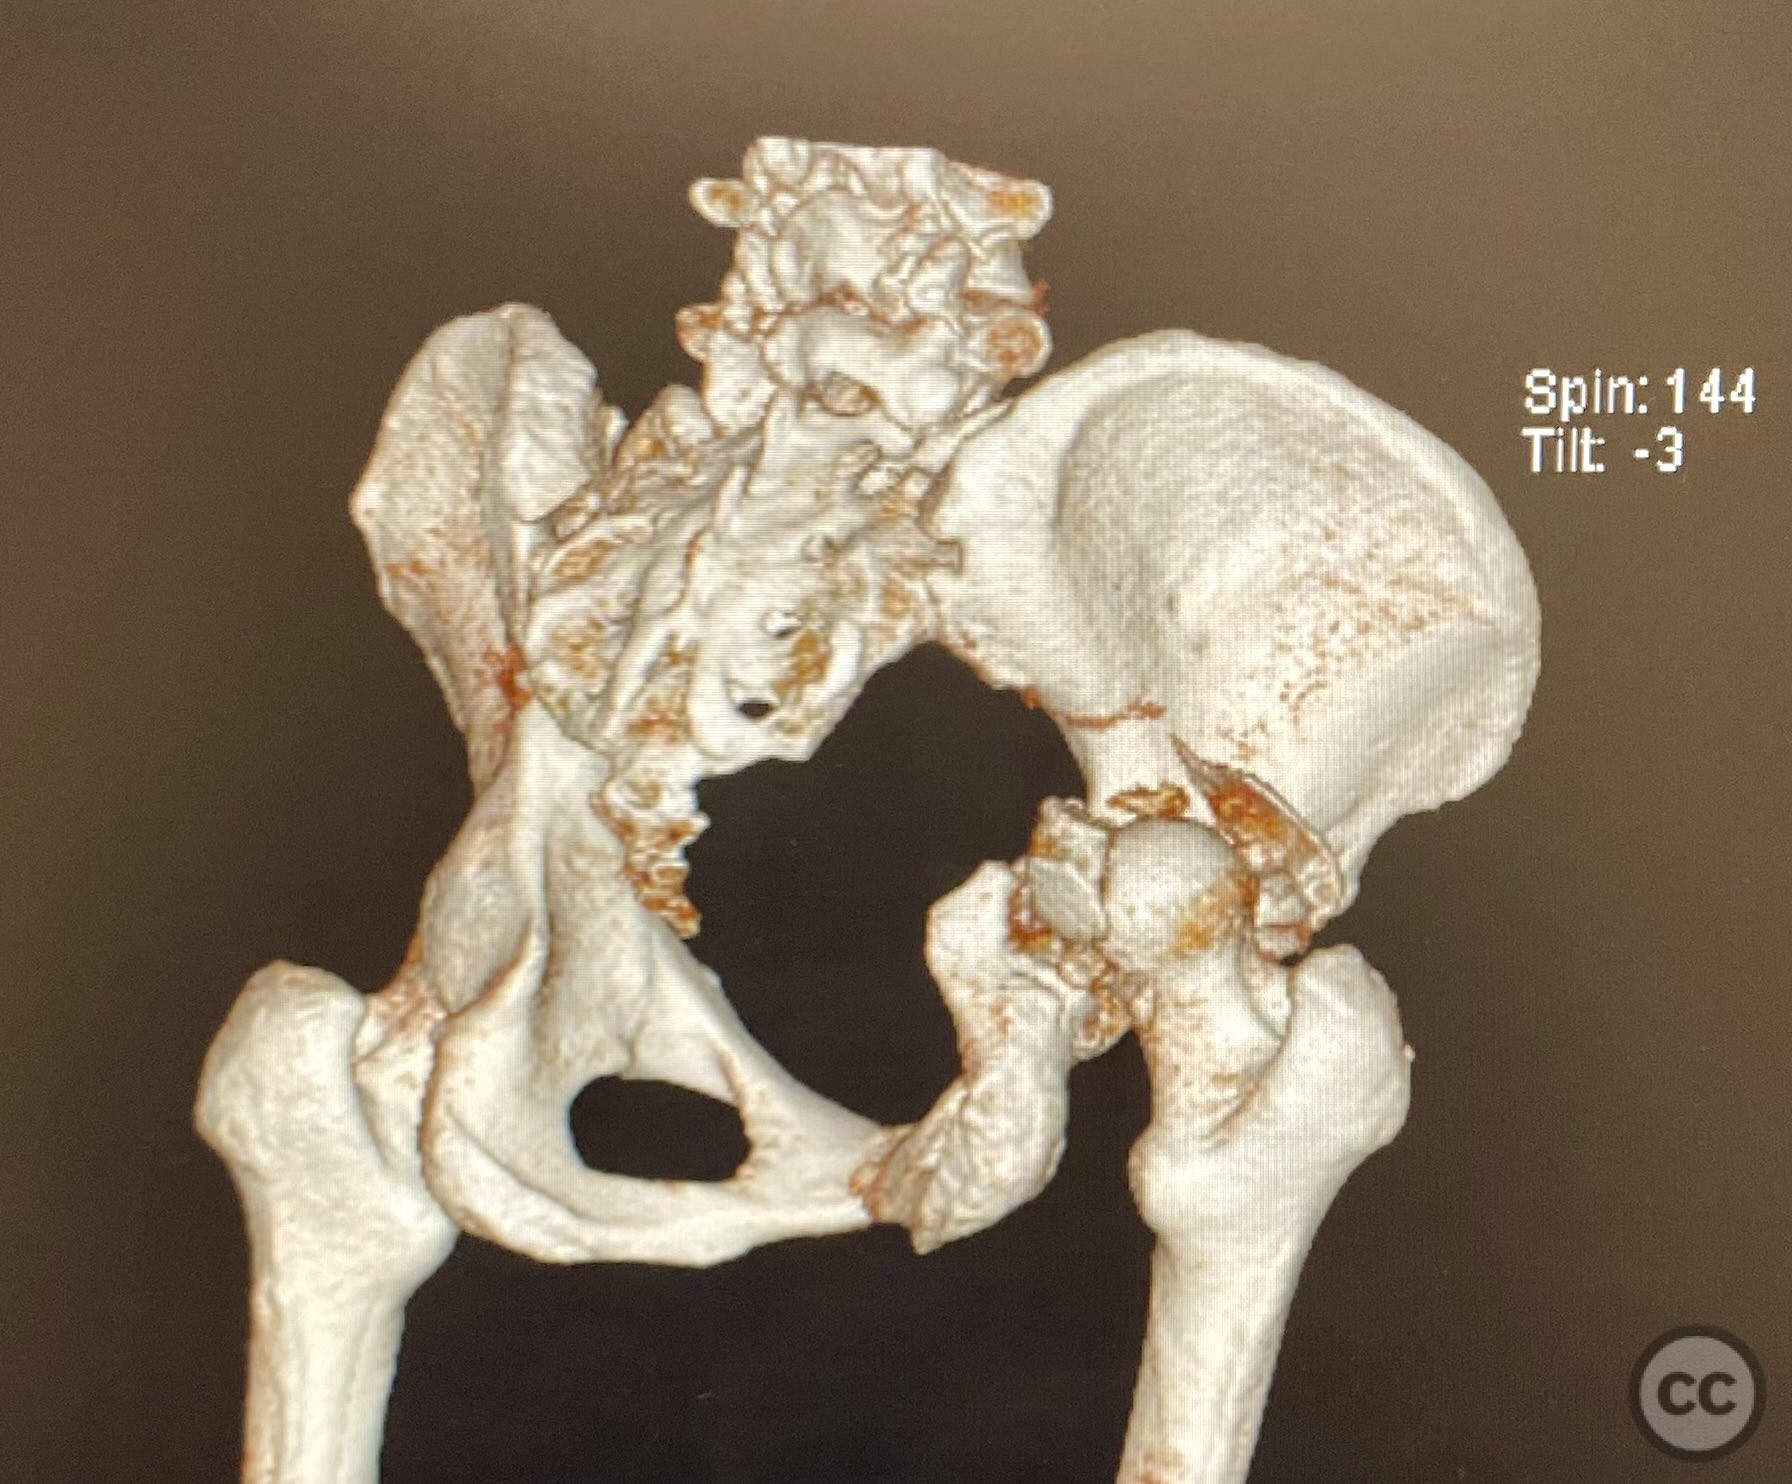

Clinical and radiological findings:  A high-speed motor vehicle collision resulted in a closed transverse acetabular fracture with associated comminuted posterior wall (PW) fracture-dislocation. The femoral head exhibited impaction and comminution, with local cancellous bone crushed and the femoral head itself also sustaining compressive injury from the denser acetabular bone. Neurovascular examination was unremarkable. Initial CT imaging delineated the acetabular fracture planes, displacement, comminution of the posterior wall, femoral head impaction, and absence of soft tissue attachment to the caudal PW fragment.

Planning remarks:  The preoperative plan was for open reduction and internal fixation via a posterior approach, specifically a Kocher-Langenbeck (KL) exposure, to allow direct visualization and manipulation of the transverse fracture plane and posterior wall fragments. Percutaneous biplanar fluoroscopy-guided cannulated cancellous lag screw fixation was planned for the transverse component, with subsequent buttress plating of the posterior wall fragments.